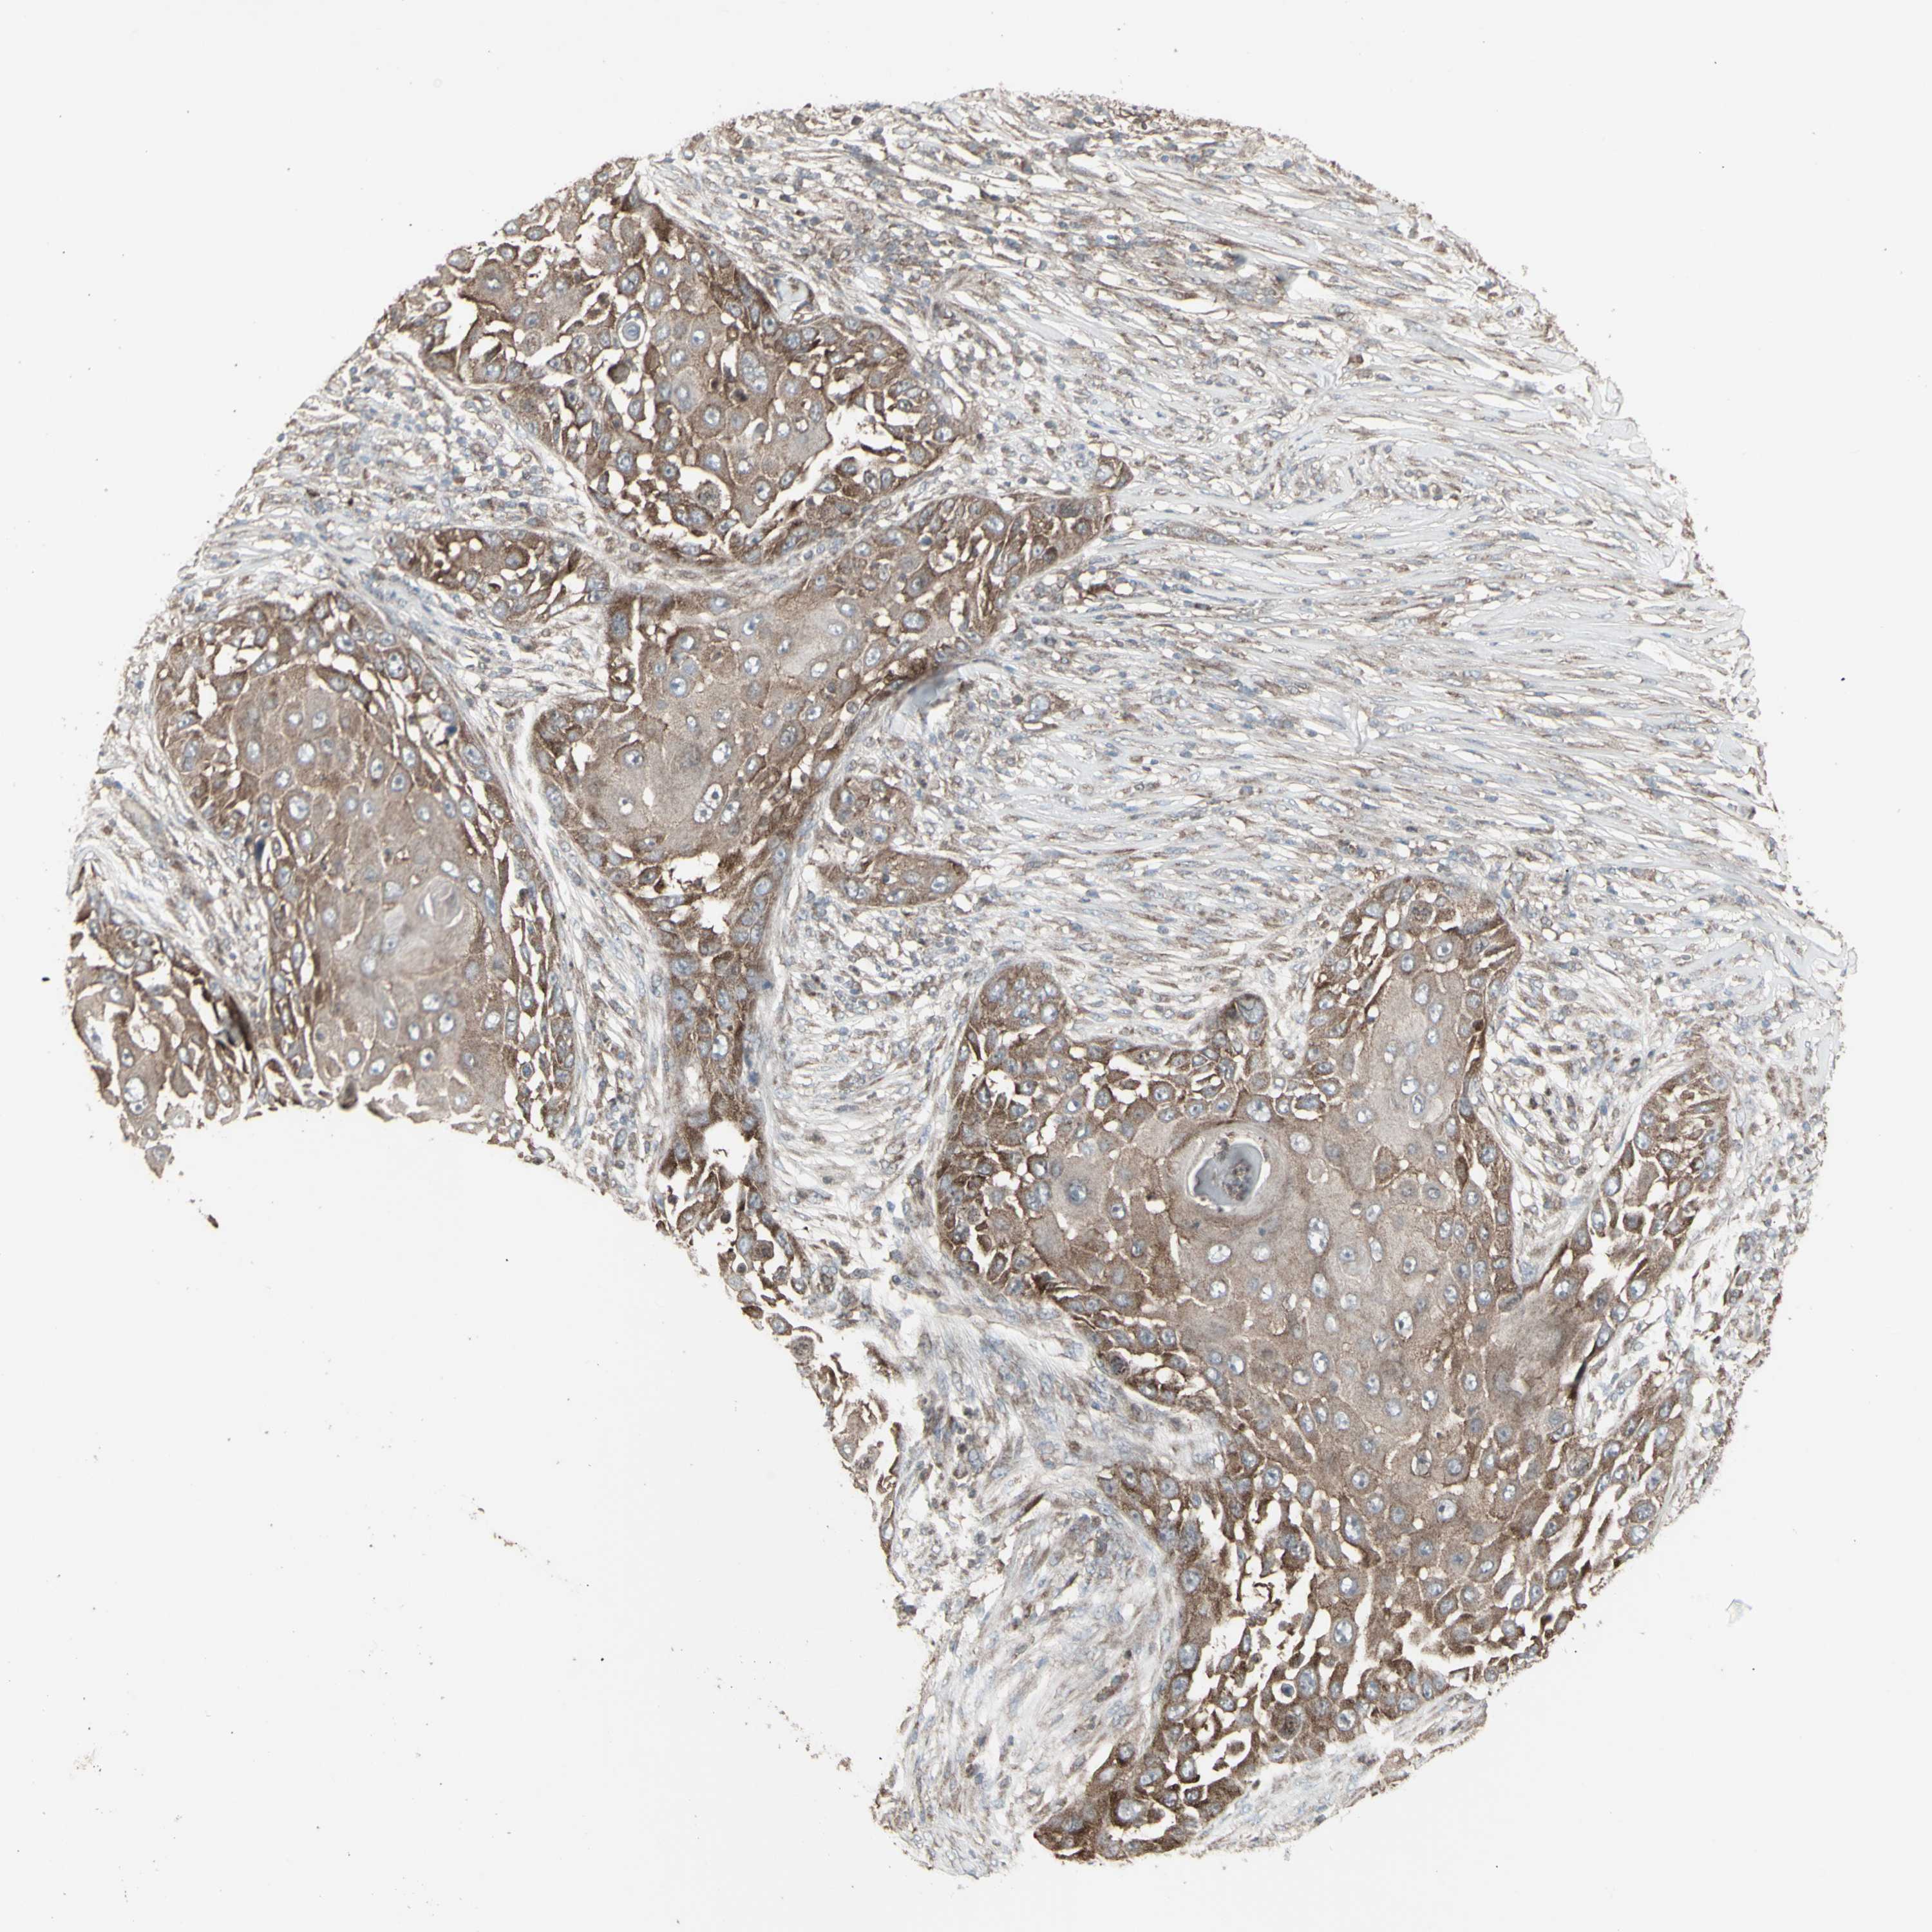

CANCER SKIN CANCER Show tissue menu

SKIN CANCER - Protein expressioni

A mouse-over function shows sample information and annotation data. Click on an image to view it in a full screen mode. Samples can be filtered based on level of antibody staining by selecting one or several of the following categories: high, medium, low and not detected. The assay and annotation is described here.

Each image is clickable and will lead to virtual microscopy that enables deeper exploration of all samples and also displays staining intensity scores, fraction scores and subcellular localization as well as patient and tissue information for each sample.

Antibody HPA002633

Squamous cell carcinoma, NOS